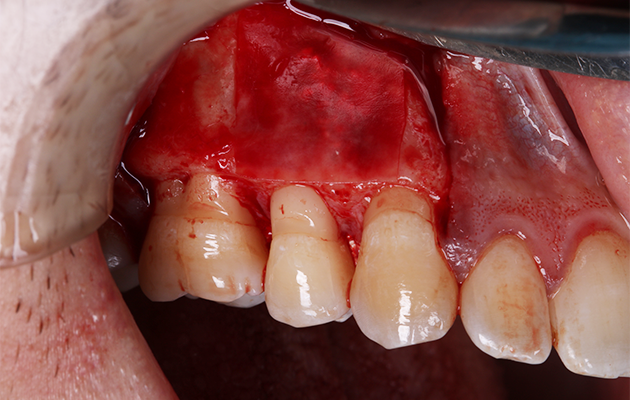

15 | Tamponamento da janela vestibular com Duosynt

16 | Membranas de L-PRF comodadas sobre a membrana sintética.